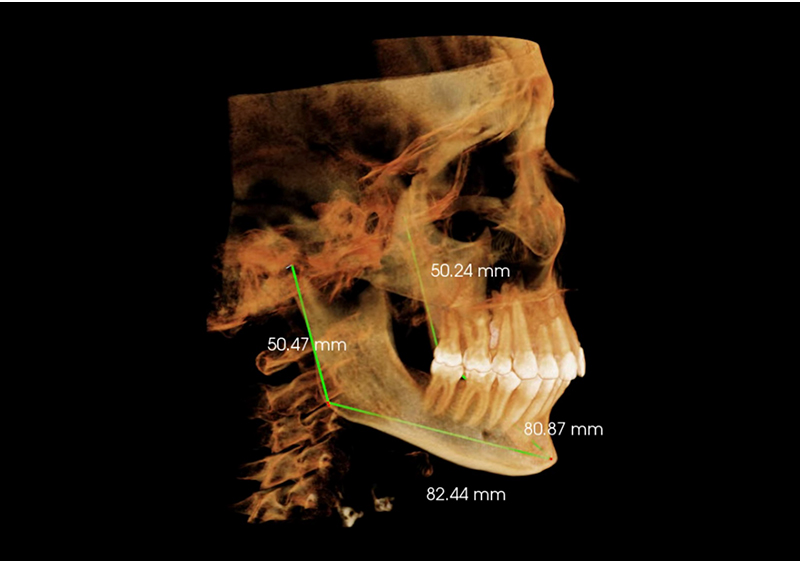

Estudio de Simetría

Nos permite analizar las distintas estructuras craneofaciales y su

relación entre si, para determinar biotipos faciales y predecir líneas de

crecimiento y desarrollo, además de posibles compensaciones